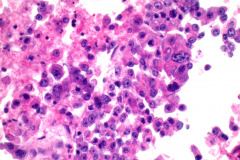

HCC has 3 main patterns: trabecular, pseudoglandular (acinar), and compact.1 Bile is prominent in some tumors, and cytoplasmic inclusions such as Mallory hyaline bodies, globular hyaline bodies, pale bodies, and ground glass are possible.1 HCC can present in a wide range of appearances, from poorly to well differentiated.1 Well differentiated HCC is highly cellular with an architecture that has isolated cells, naked nuclei, trabeculae surrounded by endothelial cells, pseudoglandular structures, transgressing vessels, and irregularly arranged sheets.1 HCC cells can retain benign hepatocellular criteria including polygonal shape, abundant eosinophilic granular cytoplasm, increased nuclear to cytoplasmic ratios, large round nuclei with prominent nucleoli, intranuclear pseudoinclusions, and intracellular bile1. Poorly differentiated HCC tends to be highly cellular with isolated cells or clusters and has pleomorphism, atypical mitoses, giant cells, spindle cells, bile, and less obvious hepatocytic differentiation.1 HCC cells tend to stain positively for HepPar1, ARG-1, CAM 5.2, and CEA.1 Positive expression of albumin by in-situ hybridization has also been shown to be a robust marker for HCC and can be more sensitive and specific in comparison to ARG-1 and HepPar1.7

In metastatic HCC, the cytologic criteria and immunophenotype are similar to that of primary HCC, however, loss of expression of the traditional immunohistochemical stains can occur.2 Cytologic specimens have an architecture of single tumor cells, trabecular pattern, traversing capillaries, surrounding endothelium, and naked nuclei.2 Cells have cytoplasmic vacuolization, prominent nucleoli, and giant tumor cells.

The cytologic features of this case were tumor cells singly or in groups, prominent nucleoli, granular cytoplasm, traversing capillaries, and some surrounding endothelial cells. The IHC staining of the lymph node biopsy determined that the cells were positive for CAM4.2, glypican-3, and focally positive for arginase while negative for HepPar-1, NKX3.1, TTF-1, and p40. In-situ hybridization for albumin was also positive.